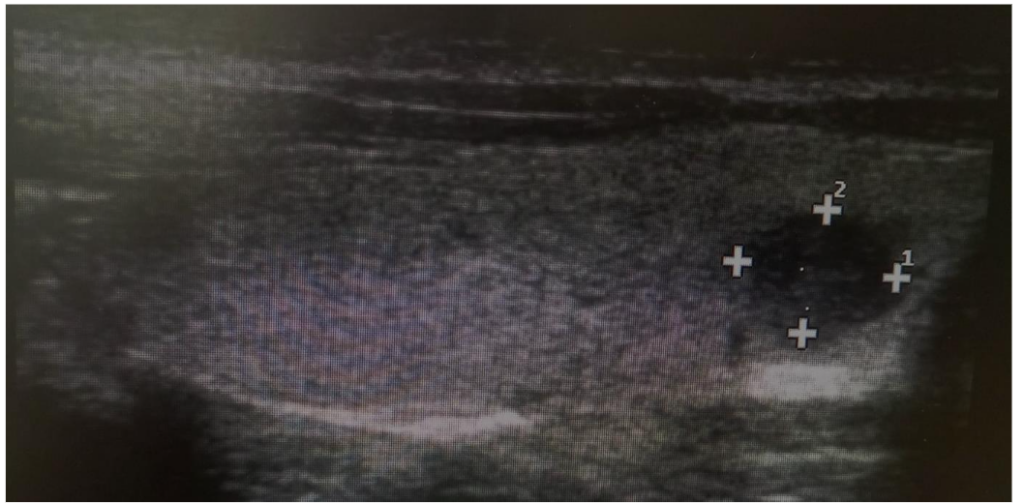

Figure 2. A Sample of Sagittal View of Thyroid Sonogram for A 22 years, Female Participant Demonstrating a Solitary Solid Nodule.